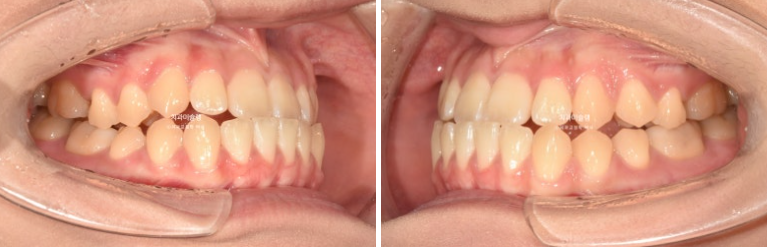

23년 9월 재교정을 결심하신 분 입니다.

23.09

어릴때 교정을 했었고 아래턱이 자라 앞니가 거꾸로 물리게 되었습니다.

측방치군, 즉 송곳니와 작은어금니에 개방교합이 보입니다.

아래 앞니가 위 앞니보다 앞에 물려 거꾸로 물림, 반대교합이 보입니다.

아래 매복 사랑니가 있어서 사랑니를 발치하고 사랑니 공간으로 아래 전체치열을 뒤로 미는 교정이 필요합니다.

기존에 붙어있던 유지장치 제거 후 클리피씨 교정을 하기로 합니다.